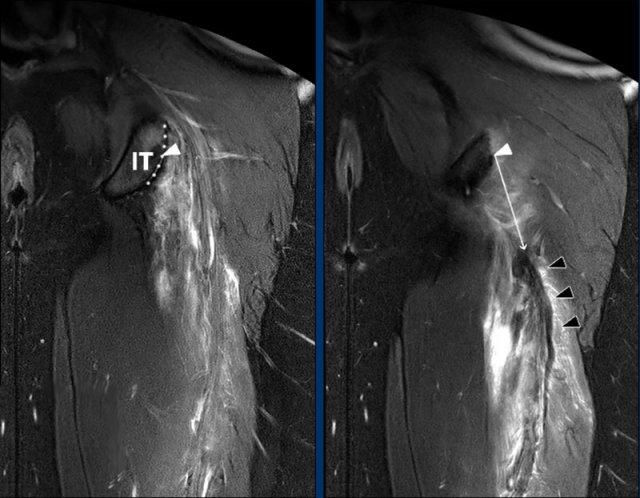

Đo trực tiếp mức độ co rút

Phương pháp đáng tin cậy nhất để định lượng mức độ co rút là ‘đo trực tiếp’ trên chuỗi xung nhạy dịch theo mặt phẳng coronal.

Đầu tiên, xác định điểm đại diện cho trung tâm (tam giác trắng) của nguyên ủy phức hợp gân cơ hamstring gần ở vùng trên (đường chấm) của củ ngồi (IT).

Từ điểm này, đo khoảng cách trực tiếp (tức là ngắn nhất) (mũi tên trắng) đến phần gần nhất của đầu gân giảm tín hiệu (tam giác đen) (tính bằng cm).

Lưu ý rằng việc xác định các mốc giải phẫu được thực hiện trên các lát cắt khác nhau trong cùng một chuỗi xung MRI.